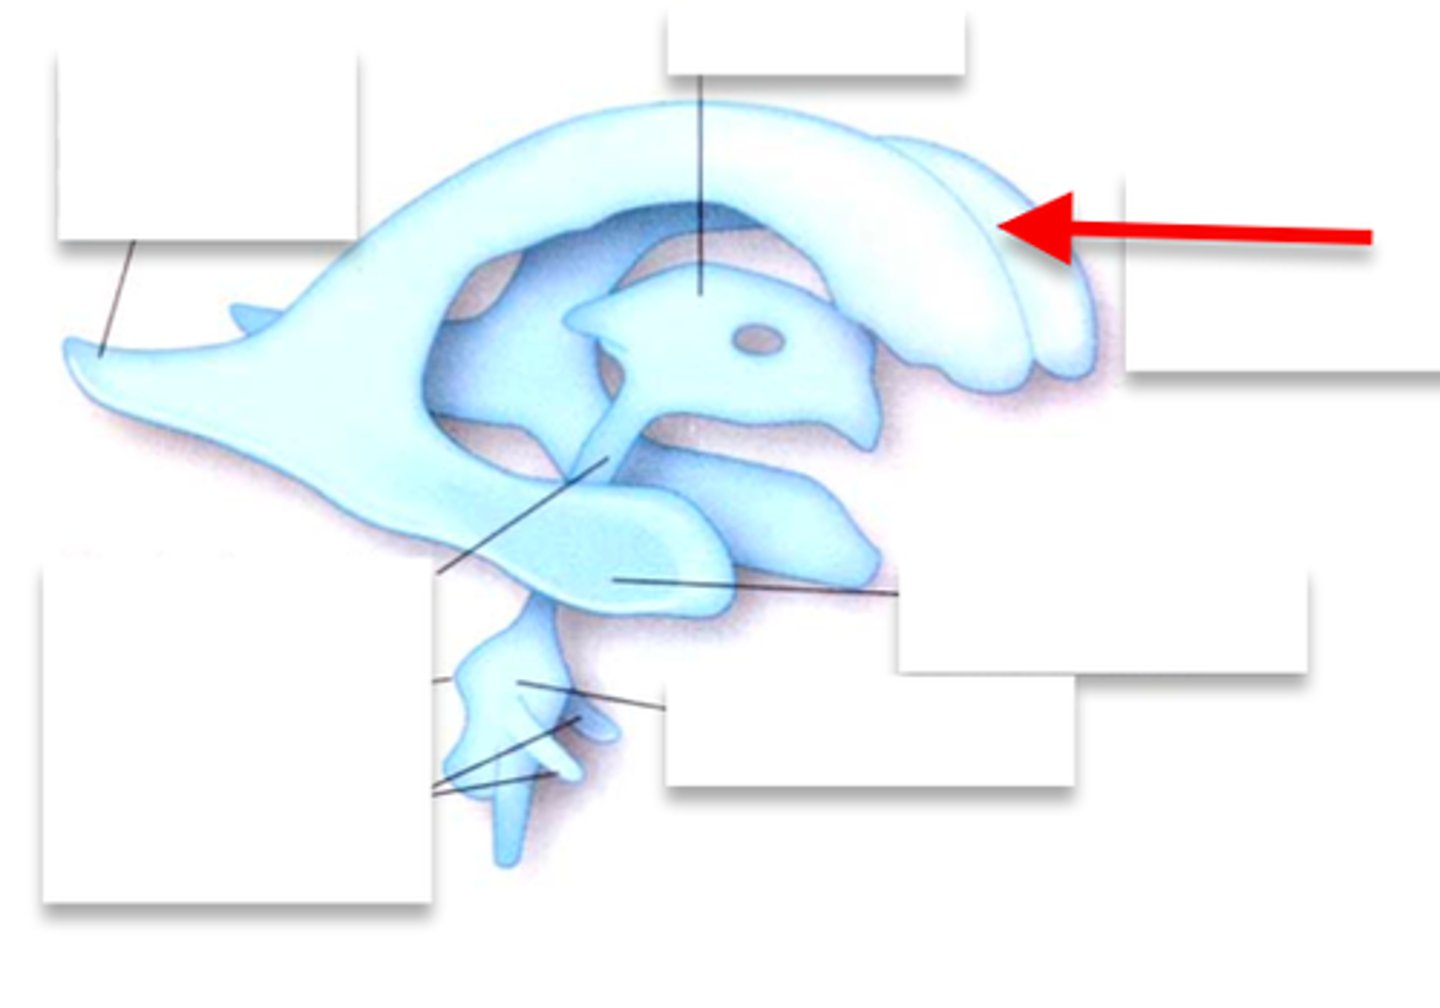

Ventricles

-Internal chambers within the brain

Lateral ventricles

-One in each cerebral hemispheres

-Interventricular foramen

Interventricular foramen

-Tiny pore that connects to third ventricle

Third ventricle

-Narrow medial space beneath corpus callosum

-Connects to cerebral aqueduct

Cerebral aqueduct

-Runs through midbrain and connects to third and fourth ventricles

Fourth ventricle

-Small triangular chamber between pons and cerebellum

-Connects to central canal that runs through spinal cord